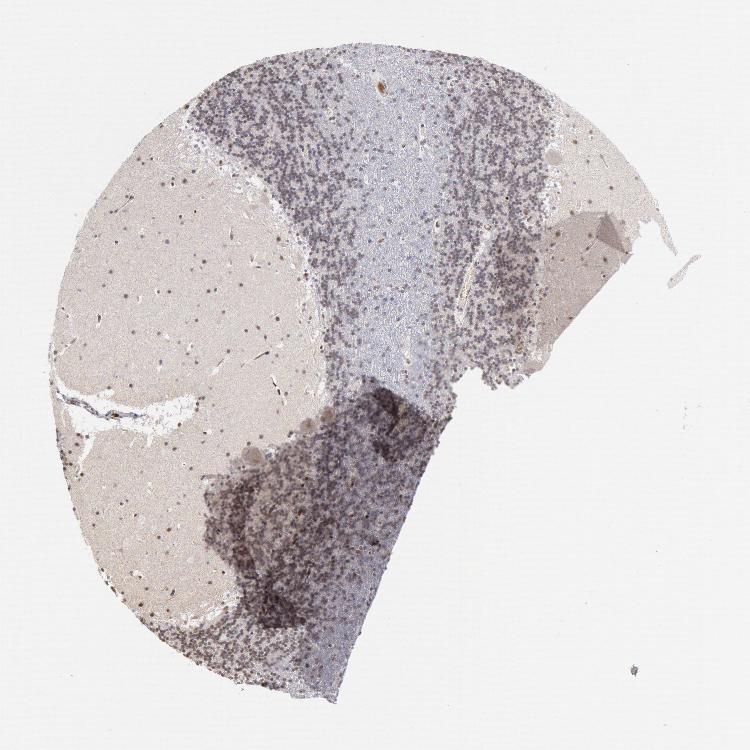

BRAIN CEREBELLUM Show tissue menu

CEREBELLUM - Expression summary

Protein expression

Cerebellumi

On the top, protein expression in current human tissue, based on all annotated cell types, is reported with the units not detected (n), low (l), medium (m) and high (h). Underneath, protein expression in each annotated cell type are reported using the same units.

Protein expression data is based on knowledge-based annotation. For genes where more than one antibody has been used, a collective score is set.

If knowledge-based annotation could not be performed for a gene, no data is displayed here. View antibody staining data further down this page.

h

m

l

n

Cells in granular layer: Not detected

Cells in molecular layer: Medium

Purkinje cells: Low

CEREBELLUM - Antibody stainingi

Antibody staining in the annotated cell types in the current human tissue is reported as not detected, low, medium, or high, based on conventional immunohistochemistry profiling in selected tissues. This score is based on the combination of the staining intensity and fraction of stained cells.

Each image is clickable and will lead to virtual microscopy that enables deeper exploration of all samples and also displays staining intensity scores, fraction scores and subcellular localization as well as patient and tissue information for each sample.

Antibody HPA001233Antibody CAB017185

Purkinje cells LowHigh

Cells in granular layer Not detectedMedium

Cells in molecular layer MediumHigh